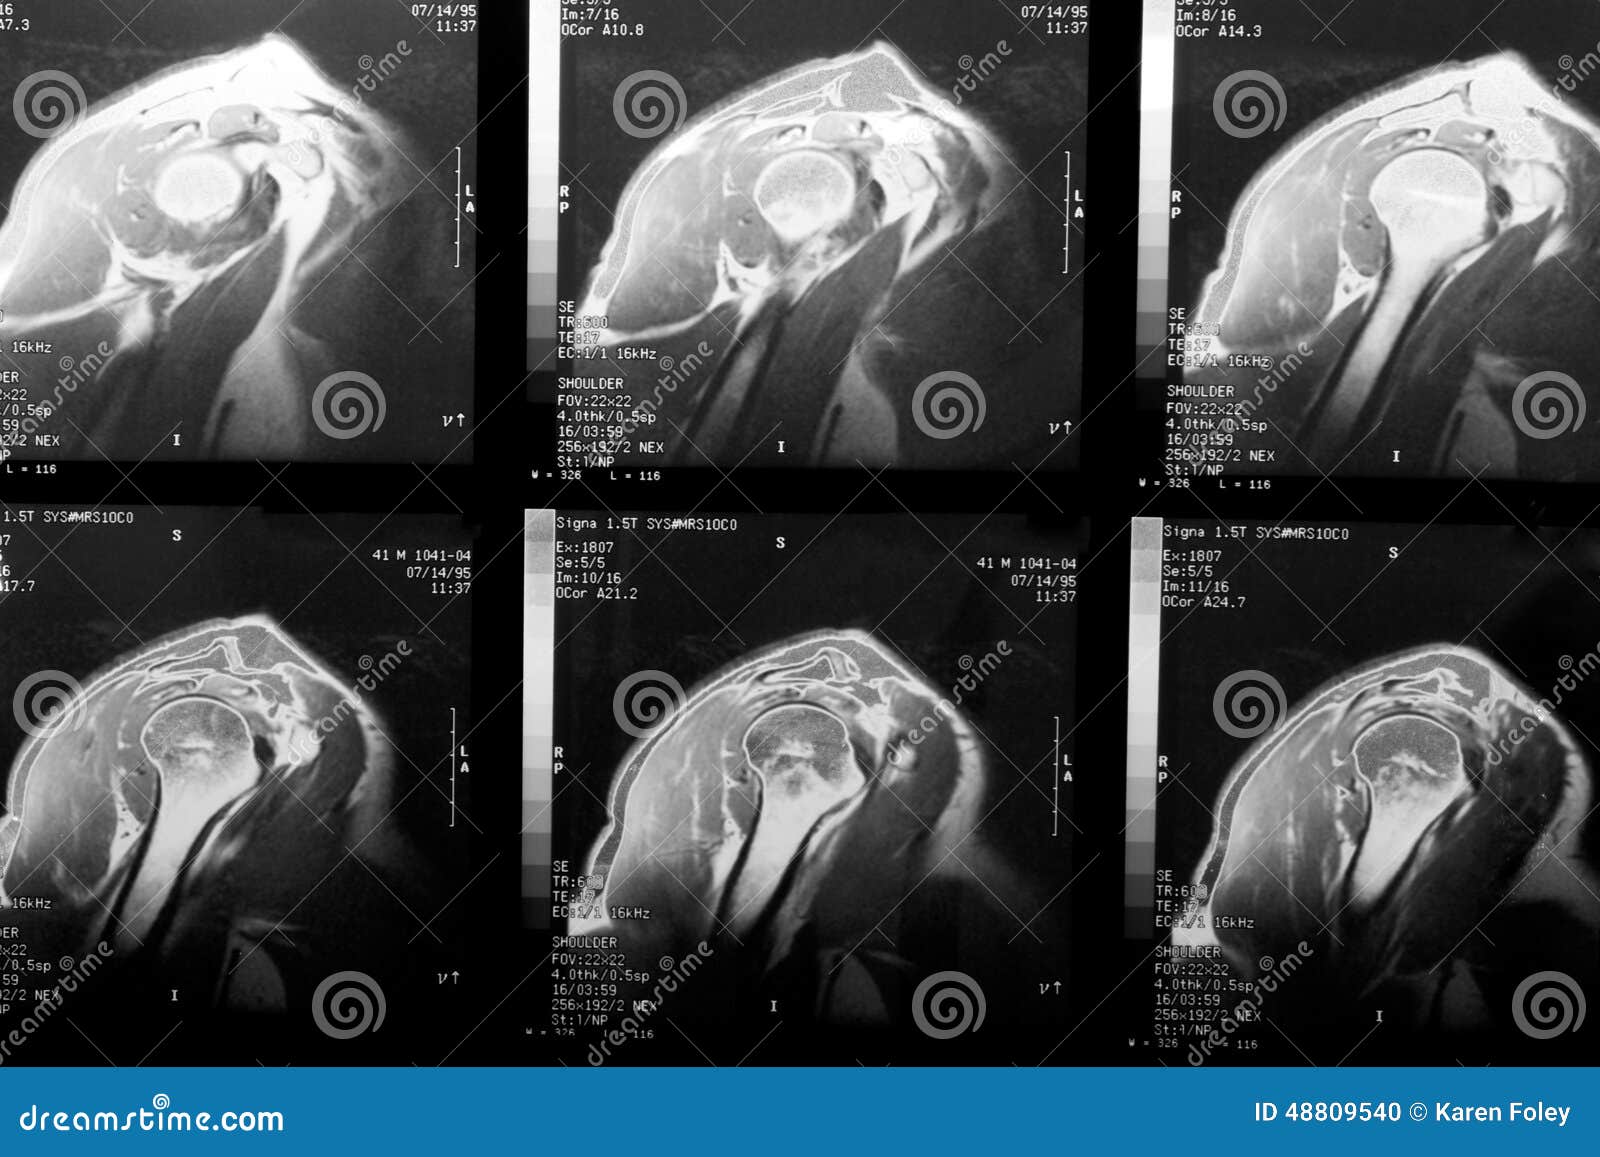

Rotator Cuff Tear MRI Images Rotator Cuff Tear X Ray Or Mri Although mra have a higher. Learn about the role of mri in detection and assessment of rotator cuff tears, impingement, biceps tendon and acromion types. Clinical and radiographic findings can suggest the presence of a rotator cuff tear. Rotator cuff tears are a common cause of shoulder pain. This article covers the anatomy, etiology,. Rotator Cuff Tear X Ray Or Mri.

Shoulder rotator cuff tear MRI Mri, Rotator cuff surgery recovery Rotator Cuff Tear X Ray Or Mri This article covers the anatomy, etiology,. Rotator cuff tears are a common cause of shoulder pain. Although mra have a higher. Learn about the role of mri in detection and assessment of rotator cuff tears, impingement, biceps tendon and acromion types. Clinical and radiographic findings can suggest the presence of a rotator cuff tear. Rotator Cuff Tear X Ray Or Mri.

Rotator Cuff Tear MRI Right Shoulder Rotator Cuff Tear X Ray Or Mri Although mra have a higher. Rotator cuff tears are a common cause of shoulder pain. Clinical and radiographic findings can suggest the presence of a rotator cuff tear. This article covers the anatomy, etiology,. Learn about the role of mri in detection and assessment of rotator cuff tears, impingement, biceps tendon and acromion types. Rotator Cuff Tear X Ray Or Mri.